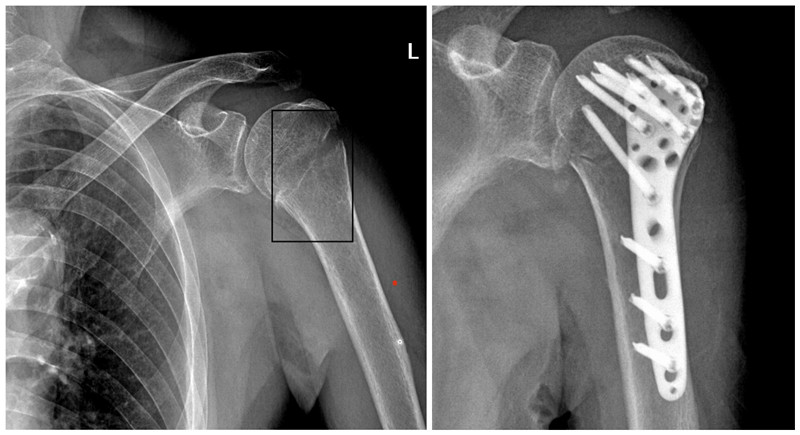

通过术前评估、血糖控制,在入院后的第三天赵顺吕医疗团队为患者进行了左肱骨切开复位内固定、左股骨转子间骨折闭合复位PFNA髓内钉手术。手术顺利结束,谢阿公返回病房,左臂的钢板与左腿的PFNA钉沉默地宣告着医学的胜利,但真正的考验才刚刚开始。病房里,时间被切割成无数个“第一次”:第一次抬腿时谢阿公额角的冷汗、第一次握紧助行器泛白的指节、第一次在护士搀扶下尝试重心转移时颤抖的呼吸……当谢阿公颤巍巍迈出第一步时,他的嘴角漏出了久违的微笑。

术前术后影像学